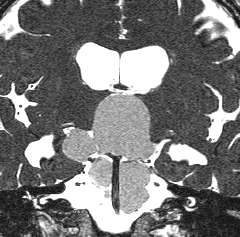

成人の第3脳室内部に局在する頭蓋咽頭腫です。経脳梁法で両側のモンロー孔から全摘出しました。下垂体組織は残っています。これは乳頭状頭蓋咽頭腫と呼ばれるもので,成人にしか発生しません,のう胞がなく石灰化もないのが大きな特徴です。境界が明瞭で柔らかく摘出が簡単なタイプとして知られています。この患者さんも術後に下垂体機能不全も視床下部障害も生じませんでした。